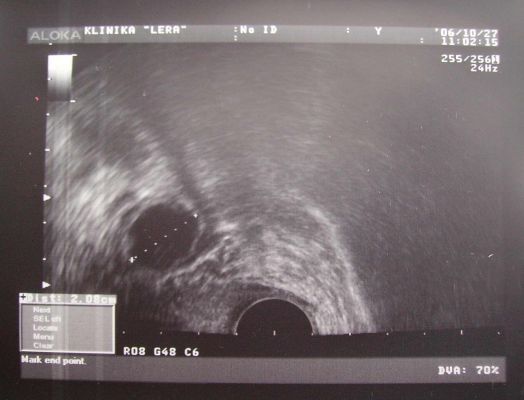

УЗИ и тест-полоски

Максимально точно определить день выхода яйцеклетки из яичника можно с помощью ультразвукового исследования. К такому способу следует обращаться женщинам, у которых наблюдается нерегулярный менструальный цикл. Проводится процедура УЗИ в несколько этапов. Начинать процесс следует через 4-5 дней после окончания критических дней. Периодичность УЗИ должна составлять 2-3 дня. С помощью исследования можно отследить развитие фолликула и момент выхода зрелой яйцеклетки из него.

Если менструация приходит регулярно, то УЗИ проводится примерно за 3-4 дня до предполагаемой даты овуляции.

Метод УЗИ

Самый точный способ определить день овуляции — это пройти УЗИ-диагностику. Здесь следует учесть, что за один день все данные получить невозможно. Для того чтобы проследить за ростом доминантного фолликула, необходимо делать УЗИ несколько дней подряд в середине цикла.

Непосредственно перед началом процесса выхода яйцеклетки на доминантном фолликуле образуется бугорок. Он хорошо просматривается на УЗИ аппарате.

Специалисты однозначно отвечают на вопросы о точном определении овуляционного процесса – нужно контролировать рост фолликулов и воспользоваться ультразвуковым исследованием. Проводят не одну, а пару процедур УЗИ. Впервые его делают на 7-8 день, второй – на 10-12, а третий – как пожелает девушка или порекомендует лечащий врач.

Первым признаком начала овуляции считается величина доминантного фолликула (значение находится в пределах от 18 до 21 миллиметров). Помимо этого, возможно перепроверить и другой факт, например, образовавшееся желтое тело означает, что овуляционный процесс прошел вполне нормально.

Ультразвуковое исследование – мониторинг

Данный способ является самым достоверным, потому что просчитать день начала овуляционного процесса благодаря фолликулограмме – очень удобно. Так, врач будет наблюдать за динамикой и разростаемостью,созреванием фолликул и выходом яйцеклетки.

Обследование считается тем же мониторингом, проводящимся в момент наблюдения за динамикой цикла. Что касается периодичности исследования, то оно происходит ежедневно с помощью специального трансвагинального датчика.

Этот способ применяется тогда, когда у девушки бесплодие или при проведении ЭКО. Данный метод способен сформировать картину о том, насколько хорошо и правильно женские органы могут работать, какая у них динамика функционирования, и наступит ли во время искусственным путем период овуляции.

При этом следует делать процедуру прибором на постоянной основе, около трех месяцев подряд. Перерывы могут быть, но не дольше, чем две недели. Благодаря такому мониторингу, девушка сможет узнать весьма ценную информацию о:

- Росте и созревании фолликула, который будет доминантным перед началом овуляционного периода;

- Появлении свободных жидкостей по окончании овуляции;

- Разрушении на стенках основного фолликула.

- Образовании желтоватого тела именно в той зоне, где созревает доминантный фолликул.

Если девушка приходит на процедуру впервые, то она должна знать, что прийти необходимо на шестой день менструации, а уже после, эту процедуру нужно будет повторять ежедневно до наступления овуляции. Что касается контрольного УЗИ, то его проводят после того, как выйдут все яйцеклетки из фолликула, на третий день.

Определение овуляции по узи

Таким образом, период овуляции – самый удачный период для зачатия ребенка. В связи с этим важно уметь определять когда происходит овуляция. Сделать это можно самостоятельно в домашних условиях, например, измеряя базальную температуру. Также разработаны особые приборы (например, ClearPlan Easy Fertility Monitor), которые по содержанию гормонов в анализе мочи способны более точно определить момент овуляции: тесты на овуляцию. Более точные определения можно сделать в клинических условиях, например, ультразвуковым наблюдением за ростом и развитием фолликула и определением момента его разрыва.

-

ультразвуковое наблюдение (УЗИ) за ростом и развитием фолликула и определение момента его разрыва (овуляции), см фото. Ультразвуковой мониторинг созревания фолликулов является самым точным методом определения овуляции. После окончания менструации, приблизительно на 7 день цикла гинеколог проводит УЗИ с использованием вагинального датчика. После этого процедуру нужно проводить каждые 2-3 дня, для наблюдения за подготовкой эндометрия. Таким образом, удается спрогнозировать дату наступления овуляции.

При ежедневном применении либо 2 раза в день (утром и вечером) эти тесты дают хорошие результаты, особенно, совместно с УЗИ. При одновременном контроле на УЗИ, можно не тратить зря тесты, а подождать, пока фолликул не достигнет примерно 18-20 мм, когда он способен овулировать. Тогда можно начинать делать тесты каждый день.